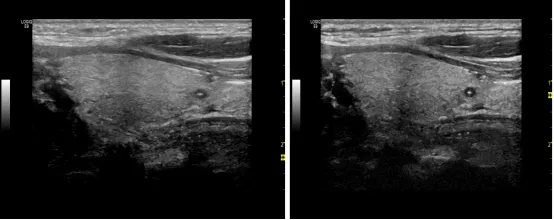

, e# N# T2 H1 j& g: f0 k2 v8 V6 y 灰阶图(Gray Map/Color maps)

, j/ X/ [, H; A: w* d3 ]% b% L 系统检测到的超声波的振幅随着信号强度的对数而变化。我们所看到的灰阶图是信号处理后的结果,操作者可根据患者的类别来选择最佳图像的设置。心脏灰阶图能更好地观察血液组织边界以及弱反射层中分散回声的细微区别,例如心肌层。建议超声心动图技术运用应与仪器生产商的应用专家合作,确定选取最佳灰度模式,并保持一致性,以便与之前的研究进行纵向比较。 0 K$ V& t: O" R7 z# L

伪彩(Colorize/Tint Map) 4 H7 Y$ o' t, k& s1 v

伪彩可能是一部分医生的偏好选择,把灰阶图转化为一系列彩色图像(如:麦黄色,深褐色,浅粉色,冰蓝色等)。他们认为彩色图像比灰阶图能更好地展示特定的结构。  & R% S' ]( V( {. w1 y3 M; }